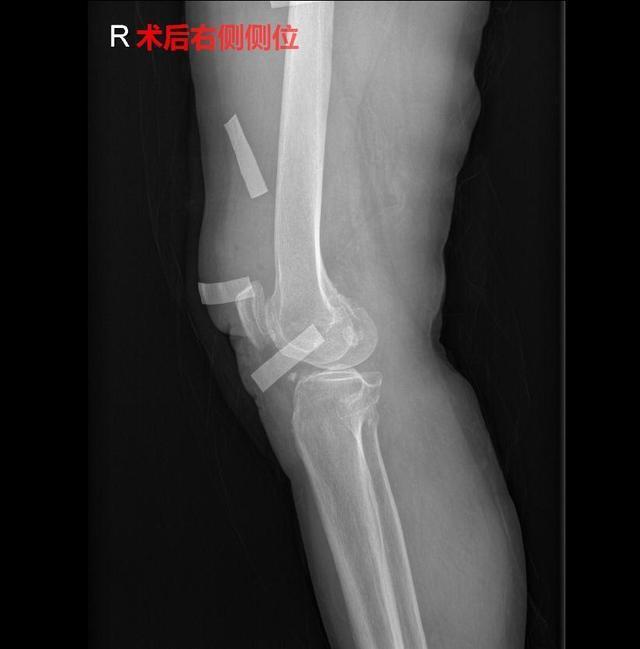

完善检查后,与家属沟通,随后进行手术治疗,在腰麻下行右膝关节镜检治疗术+切开清理术,术中见右膝关节内滑膜增生,关节内多发软骨性、骨性游离体,各骨关节软骨磨损剥脱,骨赘形成。予清理滑膜,取出游离体,切开探查并清理股骨内外侧骨赘,术后予止痛、止吐、护胃、补液等对症治疗。

目前,患者术后恢复良好,右膝切口轻微疼痛,右膝肿胀,未见明显手术并发症,已可下地活动。建议患者注意休息,均衡饮食、加强营养,循序渐进行患肢功能恢复锻炼,避免摔跤及剧烈运动。